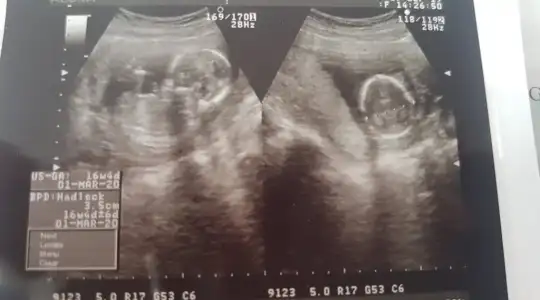

merhaba dün 2 farklı yerde ultrason çektirdik ama cinsiyetini öneremedik rica etsem usg bakıp tahmininizi söyliyebilirmisiniz 16. haftayıda geçtik hayırlısıyla teşekkkürler.

merhaba dün 2 farklı yerde ultrason çektirdik ama cinsiyetini öneremedik rica etsem usg bakıp tahmininizi söyliyebilirmisiniz 16. haftayıda geçtik hayırlısıyla teşekkkürler.Eki Görüntüle 2309422